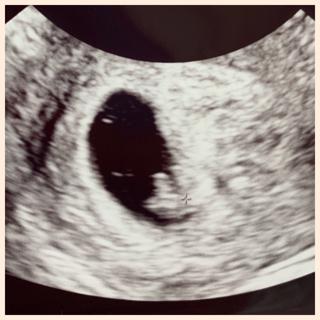

無事に胎芽・心拍を確認できました!

前回の5w5dでは胎嚢と卵黄嚢のみでしたが、2週間でしっかりと赤ちゃんが見えて感動しました!

胎芽13.4mm!

前回の妊娠は胎嚢確認後の流産だったので、まだまだ不安は大きいですが一歩先に進めてホッとしています。